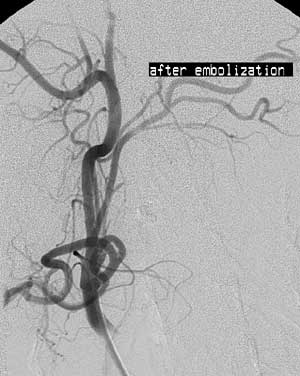

Ангиография в диагностике и лечении параганглиом области головы и шеи.

Рис. 3. Артериография наружной сонной артерии после эмболизации. Опухоль не визулизируется.